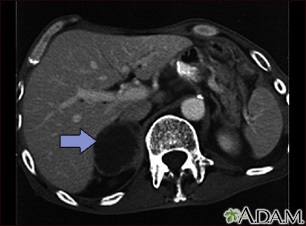

This CT scan of the upper abdomen shows an adrenal metastasis (spreading of a tumor to the adrenal gland, above the kidney) in a person with lung cancer.